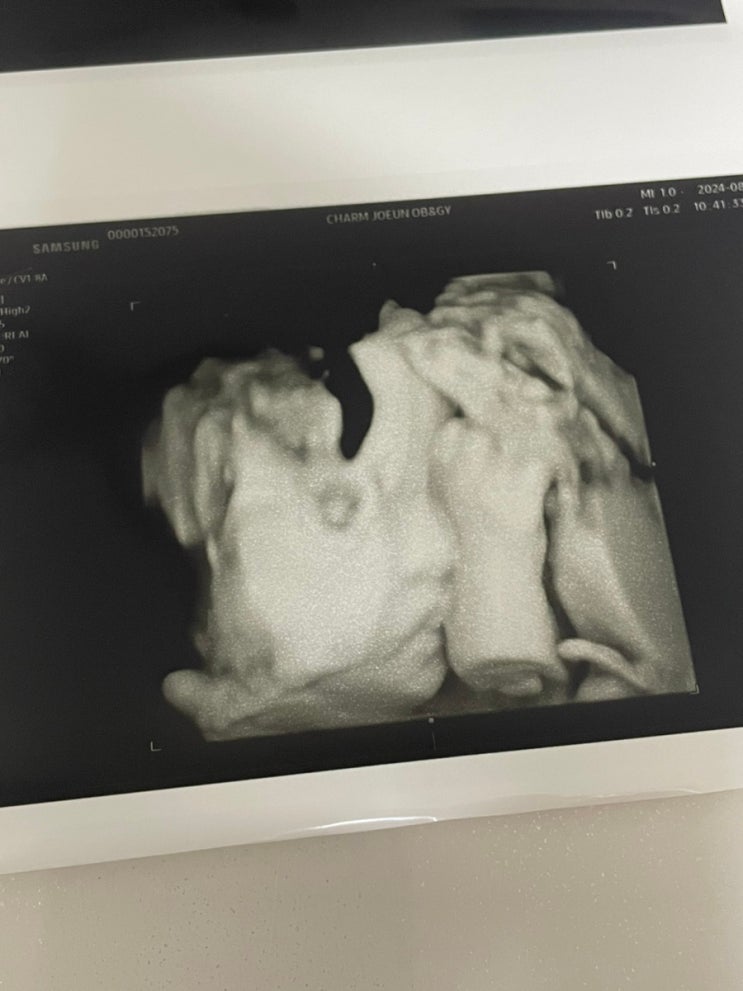

#진주참조은산부인과제왕후기 38주가 되니 아기가 많이 커져 태동도 강해지고 방광을 건들이는건지 ㅋㅋㅋ...

[임신기록]33주~37주 선택제왕 전 마지막 검진

#임신막달증상 무사히 접어든 33주 배가 진짜 남산만해지고 삼용이의 태동도 이전보다 훨씬 강해졌다. 가게...